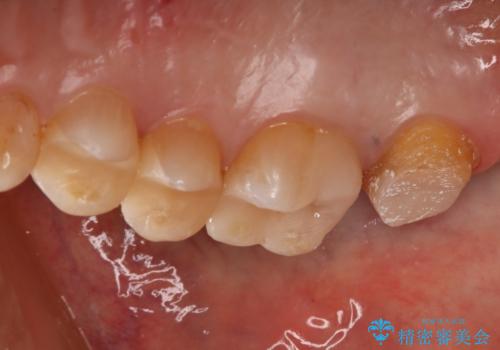

- かなり昔に入れた銀歯の部分のチェックをご希望でご来院されました。

上下ともに銀歯が多く入っており、その下に虫歯が疑われる状態でした。

詰め物の大きさや虫歯の状態から個々に材料と治療範囲を決定し治療に入りました。

- 税込 ¥88,000 - (右上第二大臼歯のセラミッククラウン1本分の費用)費用は治療当時の料金となります